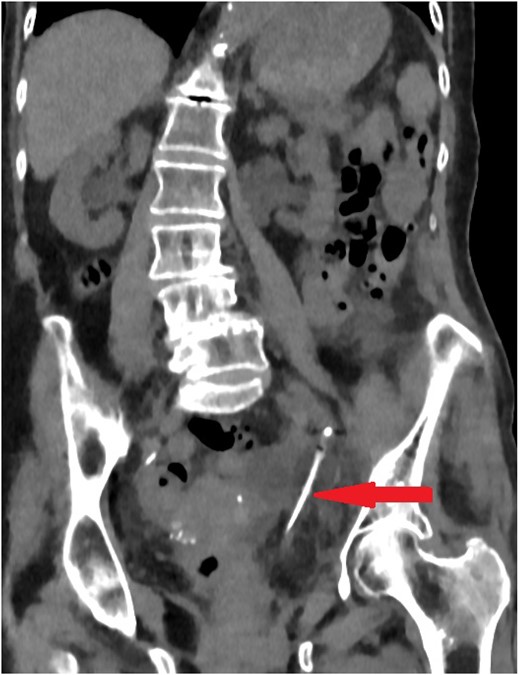

On examination, the patient was feverish (temp 38.2) and had left sided abdominal pain without tenderness on palpation. Her blood investigations did not show any significant changes. Initial washout through the catheter increased the pain and it showed passive drainage only. Non-contrast computed tomography (CT) was performed to assess the catheter position. Surprisingly, the catheter was passing into the left ureter with the catheter balloon inflated in the mid-ureter (Fig. 1).

Coronal section of abdomen and pelvis non-contrast CT: The urethral catheter migrates into the left ureter up to the mid-ureter.